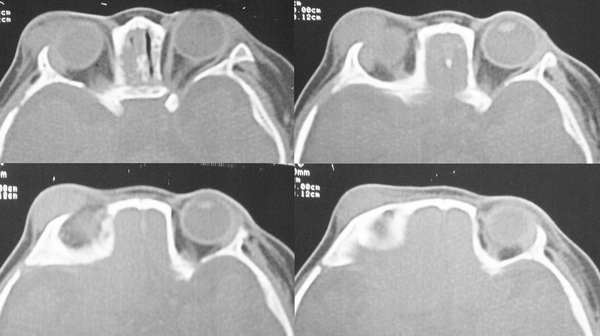

4m发现右眼周外上象限肿物年余 渐增大 软无波动

片不是很清晰,病变位置在外上象限,外直肌中远部增粗,但主要是向外膨胀,边光整,骨质无殊,与颅内无明显相关,以右侧泪腺区占位,混合瘤可能,做增强吧.

泪腺的肿瘤我认为完全可以排除,因为右侧泪腺显示的很好,肿瘤位置较为表浅,位于皮下,和泪腺无明显关系。该肿瘤为来源于软组织的肿瘤,软组织肿瘤种类繁多,影象学的目的更主要的是观察病变的范围和其与临近结构的关系,估计良恶性。该肿瘤边界清楚,与皮肤无粘连,无骨质侵蚀,考虑为良性,以血管瘤和神经纤维瘤的可能性略大些。

首先考虑眼眶毛细胞血管瘤。

横纹肌肉瘤多伴有骨质破坏,本例也应考虑无骨质破坏的横纹肌肉瘤。